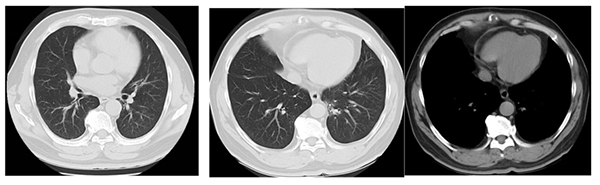

治疗7年(2025年6月)

2022年1月,复查胸部CT发现肺内新发转移灶,评估为疾病进展(PD),无进展生存期(PFS)为40个月。肺部新出现转移病灶位置难以进行肺穿刺活检,治疗团队迅速调整策略,在奥希替尼基础上联合化疗6周期(培美曲塞 + 卡铂),疗效评估为疾病部分缓解(PR),目前仍在奥希替尼持续治疗中,截至目前第2阶段持续稳定47个月,全程稳定87个月,已经超过7年3个月。

赵先生于2018年9月开始接受奥希替尼靶向治疗,肺部病灶明显缩小,最佳疗效达到部分缓解(PR),病情稳定长达40个月。期间他继续担任公园管理员,生活质量显著改善。